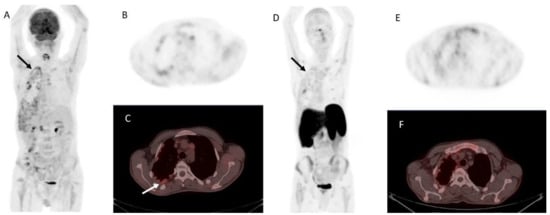

[18F]fluorocholine is a PET tracer that undergoes phosphorylation by choline kinase, an enzyme central to phospholipid synthesis in cell membranes. Hyperfunctioning parathyroid tissue—particularly adenomas and carcinomas—shows upregulated choline metabolism, leading to marked tracer accumulation. Compared to traditional scintigraphy, [18F]fluorocholine PET/CT(MR) imaging provides several key advantages: markedly improved spatial resolution (4–5 mm vs. 10–15 mm), shorter acquisition time (approximately 30 min vs. 2–3 h), higher contrast-to-background ratio, and lower radiation exposure, particularly when performed with PET/MR imaging [42]. Figure 4. demonstrates an example of PC detected on [18F]fluorocholine PET/CT.

Figure 4. A 73-year-old woman with primary hyperparathyroidism due to parathyroid carcinoma. Legend: (A) Coronal [18F]fluorocholine PET maximum intensity projection (MIP) image demonstrates an intensely tracer-avid lesion in the neck (black arrow, SUVmax 18.9). (B) Axial fused [18F]fluorocholine PET/CT image shows the tumor (white arrow) located deep to the right lobe of the enlarged thyroid gland. (C) On the corresponding unenhanced CT image, there is loss of the fat plane between the tumor (white arrows) and surrounding structures, with intralesional stippled calcifications visible (white arrowheads).

Several case reports and small cohort studies have confirmed the ability of [18F]fluorocholine PET to detect primary PC, local recurrences, regional lymph node metastases, and distant metastases to sites such as bone and lung, as well as other organs [41,43,44,45]. Notably, one case demonstrated the value of this modality in identifying an [18F]fluorocholine-positive PC metastasis in the skull base, which was subsequently removed via a transnasal-transpterygoid endoscopic approach [46]. Another report described bone and pulmonary lesions visible on [18F]fluorocholine PET but not on [18F]FDG PET/CT, highlighting the complementary role of both tracers [47].

A notable limitation, as with all radiotracers, is that [18F]fluorocholine PET cannot reliably distinguish benign adenomas from localized PC, as both demonstrate increased choline metabolism with overlapping standardized uptake values (SUV). However, the presence of a large cervical mass with intralesional calcifications, in conjunction with pathologic lymph nodes or lesions suspicious for distant metastases, is highly suggestive of PC rather than benign disease. Hence, when malignancy is clinically suspected, whole-body [18F]fluorocholine PET/CT(MR) imaging is recommended for comprehensive staging.